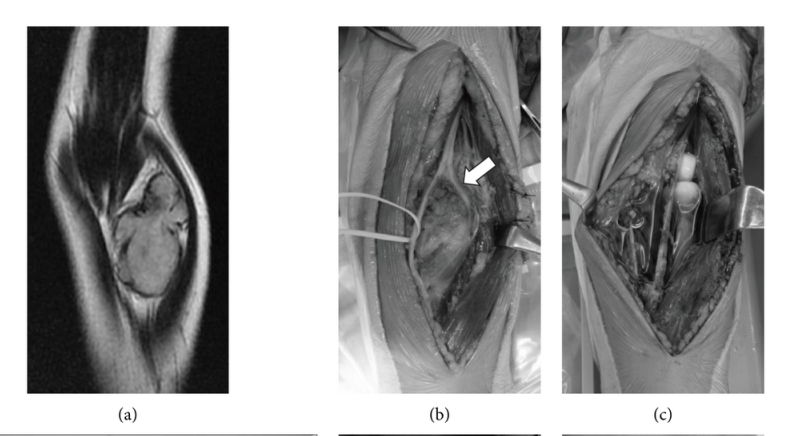

图2:23岁女性,左肘关节滑膜肉瘤(病例8)。MRI表现为T2WI(A)等信号肿块(53×32 mm)。肿瘤累及骨内后神经(白色箭头)(B)。行TE广泛切除,并联合关节囊和骨内后神经(PIN)(C)。TE患者2年后(D)出现PIN麻痹。肌腱移位术(Tsuge法)是在初次手术后2年进行的。桡侧腕屈肌(FCR)(灰色箭头)转移到拇长展肌(黑色箭头)(E)。掌长肌(黑色箭头)转移至拇长伸肌(白色箭头),而白线箭头(FCR)转移至拇长伸肌(F)。第二次手术(G)后2年,TE患者股骨头完全伸展。